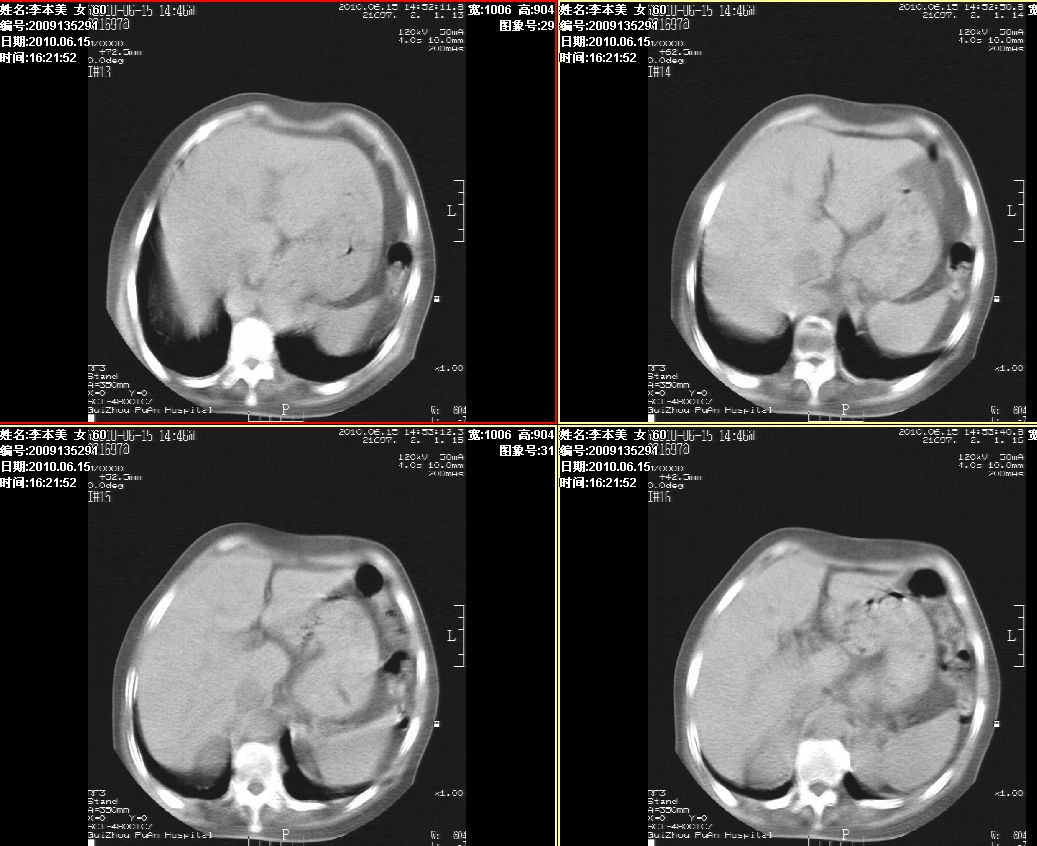

李某,60岁,女,胸闷气促一月,照片发现心后缘圆形高密度影,ct扫描如下。请大家看看,描述一下,给个诊断意见。

图像欠清,主动脉瘤?食管肿瘤?食管裂孔疝?建议增强。

考虑为:食管裂孔疝; 不排除食道下段肿瘤性病变。

考虑为:食管裂孔疝; 不排除食道下段肿瘤性病变

食管裂孔疝?钡透看看

食管裂孔疝; 不排除食道下段肿瘤性病变。

考虑食管裂孔疝, 食管下段肿瘤性病变待排;建议行进一步检查。

主动脉瘤?食管肿瘤?食管裂孔疝?建议增强。

食管癌?